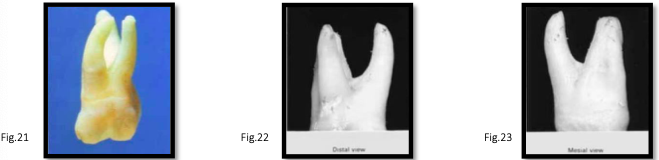

canal anatomy of mn 2nd molar

similar to first molar

distal root: lower incidence of two canals

roots: tend to be closer together [fig. 51-52]

mesial root: usually 2 canals, occasionally 1 (broad bucco-lingually)

rare variations:

single root with single canal [fig. 53]

c-shaped canals → distal canal extends mesially, sometimes including mesiobuccal and mesiolingual canals [fig. 44-45]

difficult to detect on preoperative radiographs